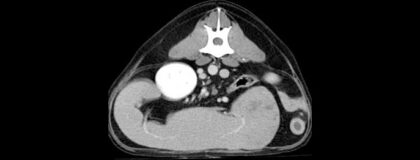

In diesem vetinar lernen Sie die wichtigsten Indikationen der CT-Untersuchung am Abdomen kennen. Anhand von spannenden Fallbeispielen werden die Einsatzmöglichkeiten der CT allgemeinverständlich erläutert. Nach einer Einführung werden zusätzlich spezielle Erkrankungen und deren spezifische Anzeichen in der CT aufgezeigt. Für Anfänger:innen und Profis gibt das vetinar anhand von „Entscheidungs-Algorithmen“ eine Zusammenfassung zur Frage „CT - ja oder nein?“. Der Abschluss wird durch eine Zusammenfassung der wichtigsten Indikationen und Befunde gebildet.